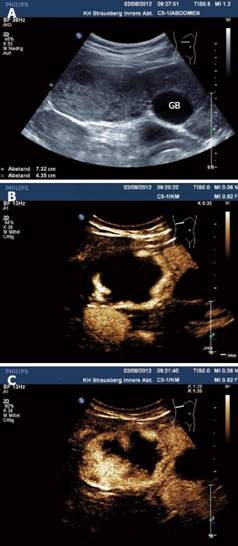

Một phụ nữ 48 tuổi phàn nàn có sự khó chịu ở vùng bụng, bệnh nhân chưa từng có các triệu chứng như vậy trước đó, biểu hiện đau ra sau lưng và cảm giác đầy bụng. Các triệu chứng của bệnh nhân đã liên tục tăng trong 5 năm qua. Bệnh nhân này đã mất sụt mất 12 pounds trong vòng 6 tháng qua. Đồng thời, bệnh nhân buồn nôn và biếng ăn/ chán năn. Đầu tiên, bệnh nhân được đưa vào một bệnh viện, sau đó siêu âm bụng và chụp cắt lớp vi tính ổ bụng (CT-scanner) được thực hiện. Siêu âm cho thấy một khối thương tổn [38 × 29 mm]. Các hình ảnh CT-scanner xác nhận phát sự hiện diện của khối này bằng cách tìm ra được một khối [3 × 4 cm] giảm dần đậm độ về trung tâm, tổn thương ở thùy trái của gan. Ngoài ra, ở vùng rốn gan, có hạch bạch huyết 31 mm đã được xác định.

Các nghiên cứu hình ảnh được lặp lại sau đó nhiều lần sau khi hội chẩn của cả nhóm. Những hình ảnh CT-scanner trước khi điều trị ban đầu cho thấy có khối rắn nhạt màu dần dần về trung tâm [7 × 5,5 cm] trong các phân thùy gan 2, 3 và 4. Các khối u cũng được tìm thấy, gây ra tắc mật ở thùy trái. Hơn nữa, hạch đã được xác định, với các hạch bạch huyết lớn nhất là 2,7 cm, đường kính trong khu vực khoang tĩnh mạch. Một xét nghiệm máu tổng thể đã được thực hiện cho thấy BCAT (2.900/mm3), chính chỉ số này gợi ý dẫn tới sự nghi ngờ của một ca bệnh nhiễm ký sinh trùng. Để cho ra một chẩn đoán xác định, nhóm nghiên cứu đã thực hiện sinh thiết. Trong việc kiểm tra bệnh lý, tổn thương một phần hình thành u hạt đó bao gồm toàn bộ BCAT và rất ít tế bào đơn nhân được xác định.

H3

Trong nhu mô gan, hình ảnh thương tổn do sán đã được xác định. Với một chẩn đoán phân biệt là ca bệnh nhiễm sán lá gan lớn Fasciola hepatica, huyết thanh chẩn đoán miễn dịch theo phương pháp và kỹ thuật (Fast enzyme-linked immunosorbent assay_FAST-ELISA) đã thực hiện nhằm thiết lập chẩn đoán cuối cùng. Sau khi chẩn đoán xác định, chỉ định liệu pháp điều trị sán lá gan lớn bằng triclabendazole (TCBZ) được chỉ định. Bệnh nhân sau đó được ra viện và yêu cầu tái khám 3 tháng sau để theo dõi diễn tiến. Kết quả của một CT-scanner khác sau đó cho thấy sự phục hồi cả khối u và các hạch lympho rõ ràng trên hình A và B.

Các chẩn đoán hình ảnh thấy chụp CT-scanner ổ bụng kiểm tra cho thấy một khối thương tổn giảm âm, giảm dần độ đậm về trung tâm 7 × 5,5 cm trong nhu mô gan. Sau đó, hình ảnh CT scanner khác cho thấy sự phục hội và xóa mờ các “khối u” ở trong nhu mô gan. Sinh thiết gan được đánh giá đối với u có tăng BCAt và cấu trúc nhu mô và giải phẩu bệnh giống như thương tổn do ký sinh trùng.